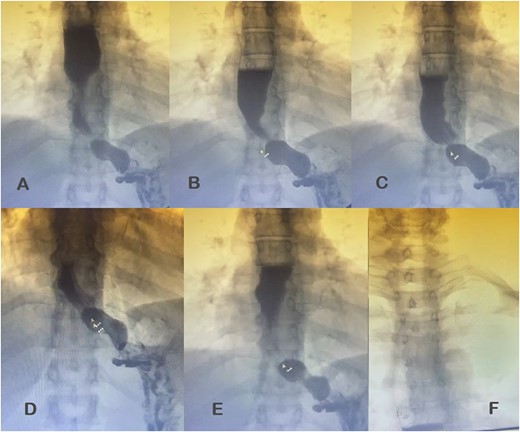

Additional diagnostic procedures included videoendoscopy, which revealed grade II megaesophagus and gastroscope-adjusted hiatus to the retroversion maneuver with signs of competent fundoplication. Esophagogastroduodenal transit with barium contrast (Fig. 1) showed adequate passage from the esophagus to the stomach with fundoplication on diaphragmatic arches, suggesting the presence of a hiatal hernia with intrathoracic stomach contents. Return of contrast after swallowing suggests reflux, presence of tertiary waves, stenotic area in cardia, and megaesophagus without alteration of gastric emptying. The patient showed normal phmetry and manometry (Fig. 2) with difficulty in passing the probe through the lower sphincter, presumably due to hypertension or lack of relaxation and esophageal body activity with panpressurization, classified as achalasia evolving from type I to type II.

Esophagogastroduodenal transit with barium contrast. (A) Enlarged esophagus; (B) area of stenosis; (C-E) fundoplication and hiatal hernia with stomach above the diaphragmatic domes; tertiary F waves.